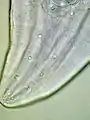

Male Gongylonema pulchrum as seen under a light microscope.[1]

These are all pictures from a single Gongylonema pulchrum male extracted from a man in France.[1]